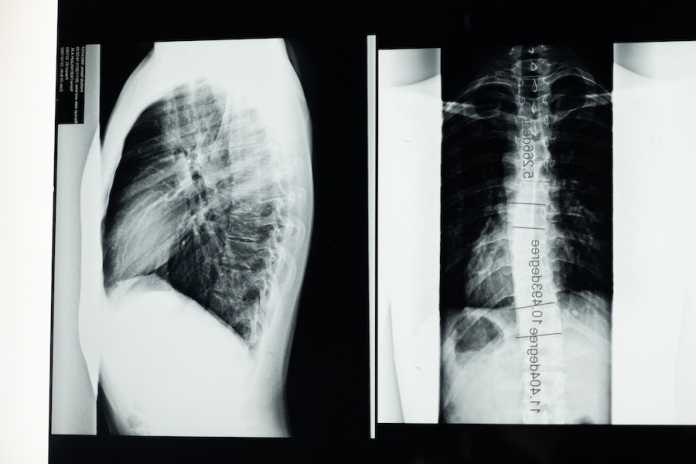

Πρόκειται για την Χρόνια Αποφρακτική Πνευμονοπάθεια (ΧΑΠ), η οποία αποτελεί χρόνιο αναπνευστικό νόσημα με περιορισμό στην εκπνοή λόγω απόφραξης ή καταστροφής τμημάτων του πνεύμονα.

Με 3,23 εκατομμύρια θανάτους από ΧΑΠ να έχουν καταγραφεί το 2019, αποτελεί την 3η αιτία θανάτου παγκοσμίως. Για τον λόγο αυτό έχει καθιερωθεί και η Παγκόσμια Ημέρα Χρόνιας Αποφρακτικής Πνευμονοπάθειας, που φέτος είναι η 17η Νοεμβρίου, με στόχο την ευαισθητοποίηση του ευρέως κοινού, αλλά και την ενημέρωση των πασχόντων ή των δυνητικά πασχόντων, έτσι ώστε να είναι σε θέση να αντιμετωπίσουν σωστά την κατάστασή τους.

Τα κύρια συμπτώματα της ΧΑΠ είναι ο βήχας, η δύσπνοια, η παραγωγή πτυέλων, η κόπωση και το σφίξιμο στο στήθος.